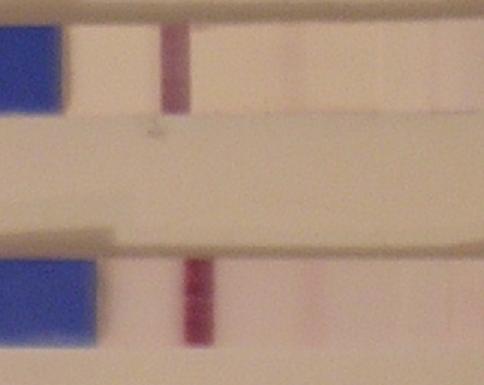

áfi, monyoka nem merek hangosan, de hallkan igen: GRATULÁLOK!!!!!

Áfi, a mai határozottan erősebb!!!!!

Monyoka, gyorsan, gyorsan másik teszt!!! Ez is sokkal erősebb lesz!!!!